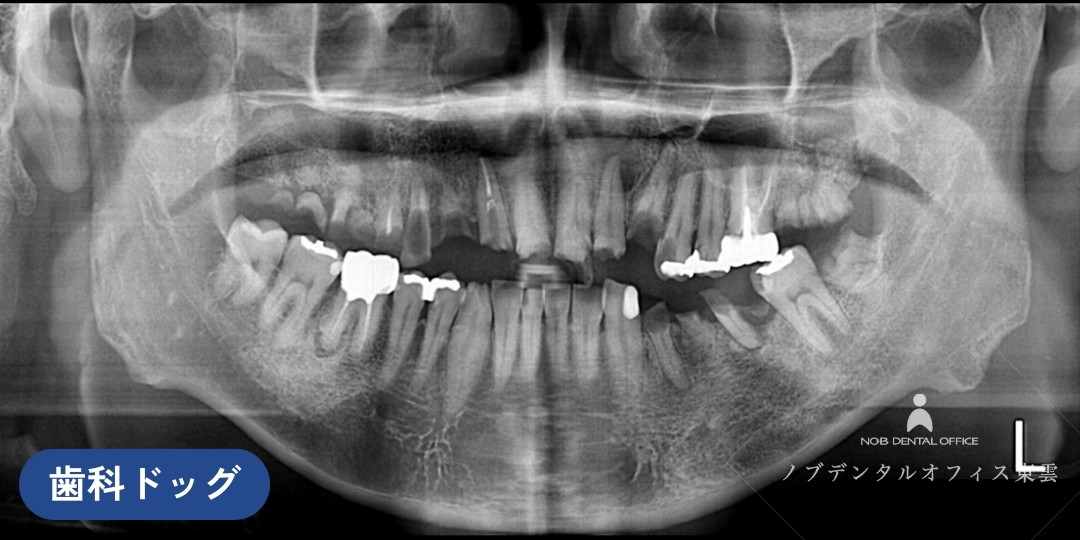

次に、口腔ドッグ・精密検査とカウンセリングを行いました

口腔ドッグで詳しく検査を行いました。

また、診察用の模型を作成し、患者様と担当医で治療のゴールを可視化しました。

検査結果を踏まえ、どんな治療が可能なのか、保険・自費の選択肢を含めてお話ししました。

レントゲン写真

精密レントゲン

3次元で診査できる歯科用CT